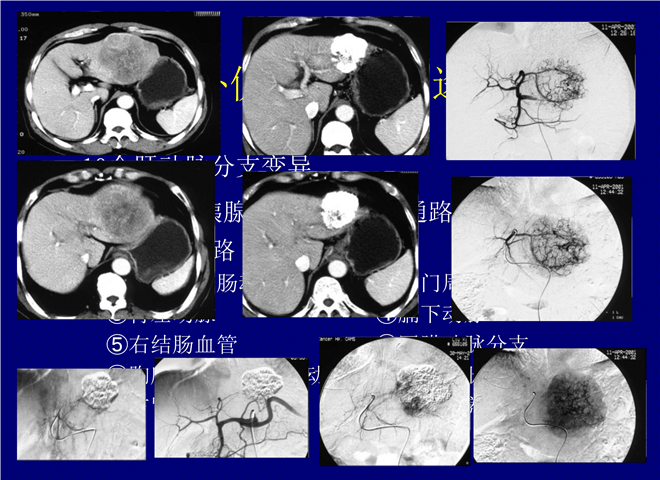

06_肝癌介入治疗-2